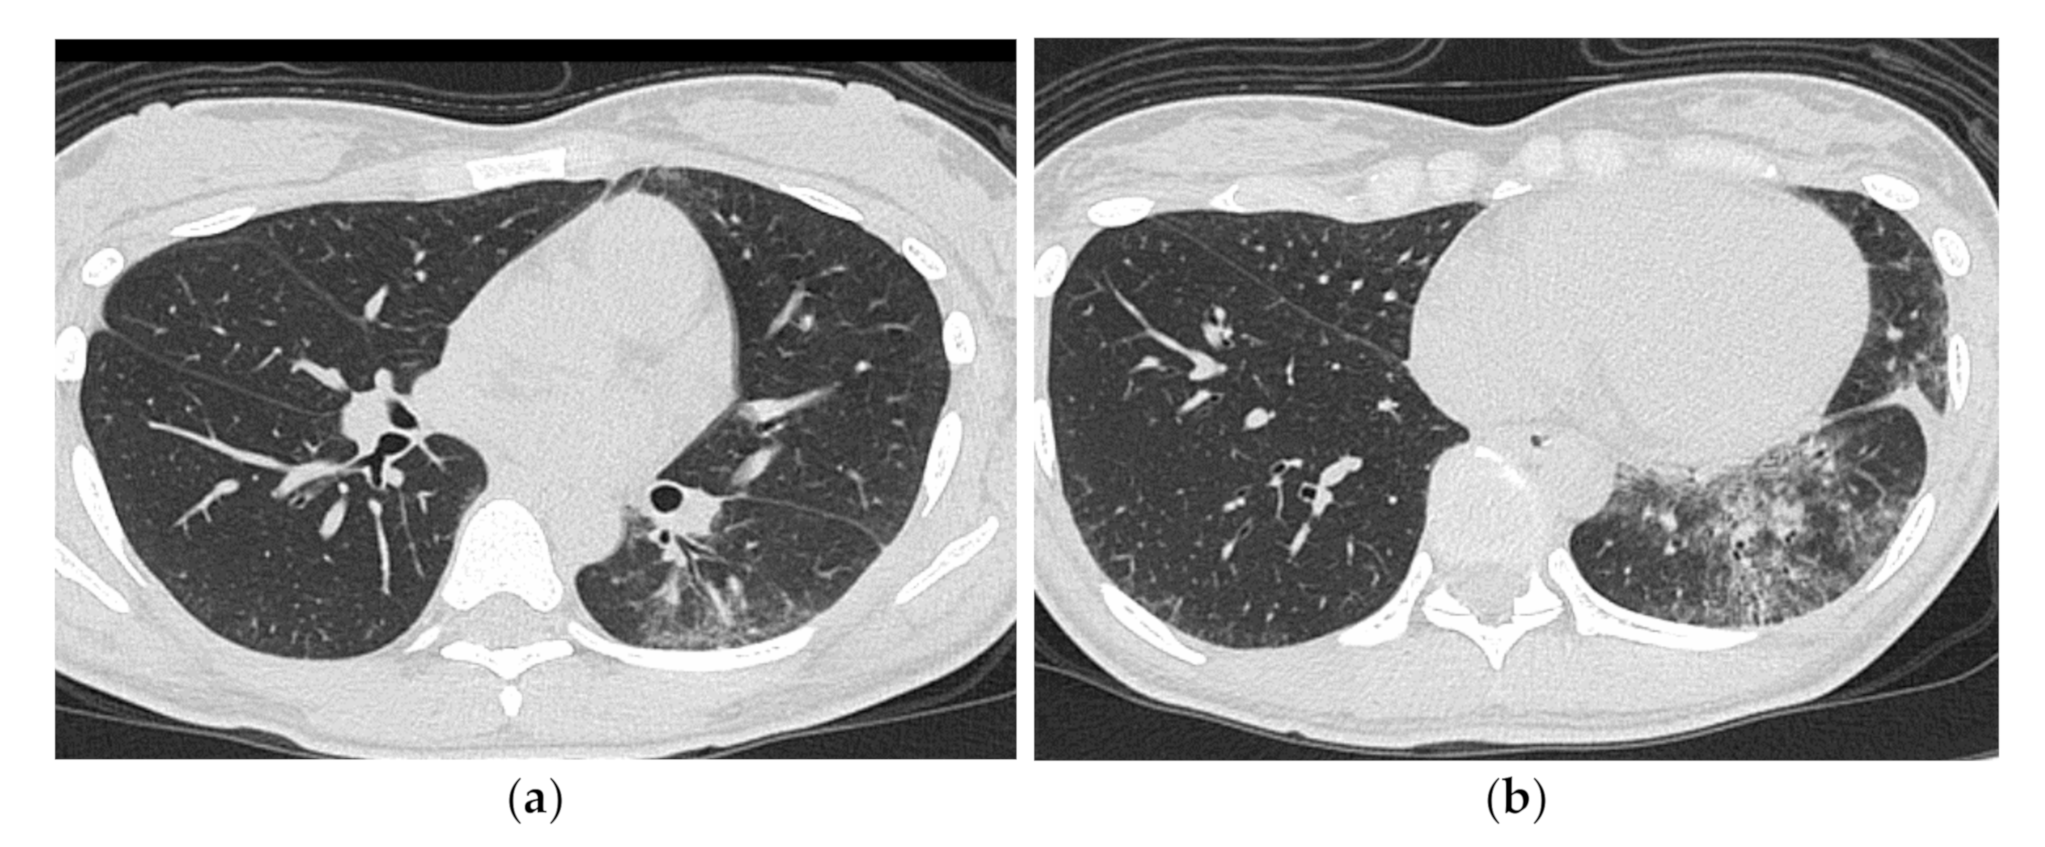

HRCT Findings of Patients with Anti-MDA5 Ab

| Anti-ARS Antibody Positive | Anti-MDA5 Antibody Positive |

|---|---|

| Chronic to subacute onset >> Acute/rapidly progressive | Acute or subacute onset, often rapidly progressive |

| Distribution along the bronchovascular bundles in the bilateral lower lung fields > diffuse | Diffuse, predominantly in the lower lung fields, or both |

| Reduced volume of the lower lobes | Peribronchovascular lesion of the periphery of lower lobes, with parallel spread to the pleura |

| Reticular shadows or consolidation > GGO | Patchy distribution |

| Good response to treatment but relapses | GGO and consolidation |